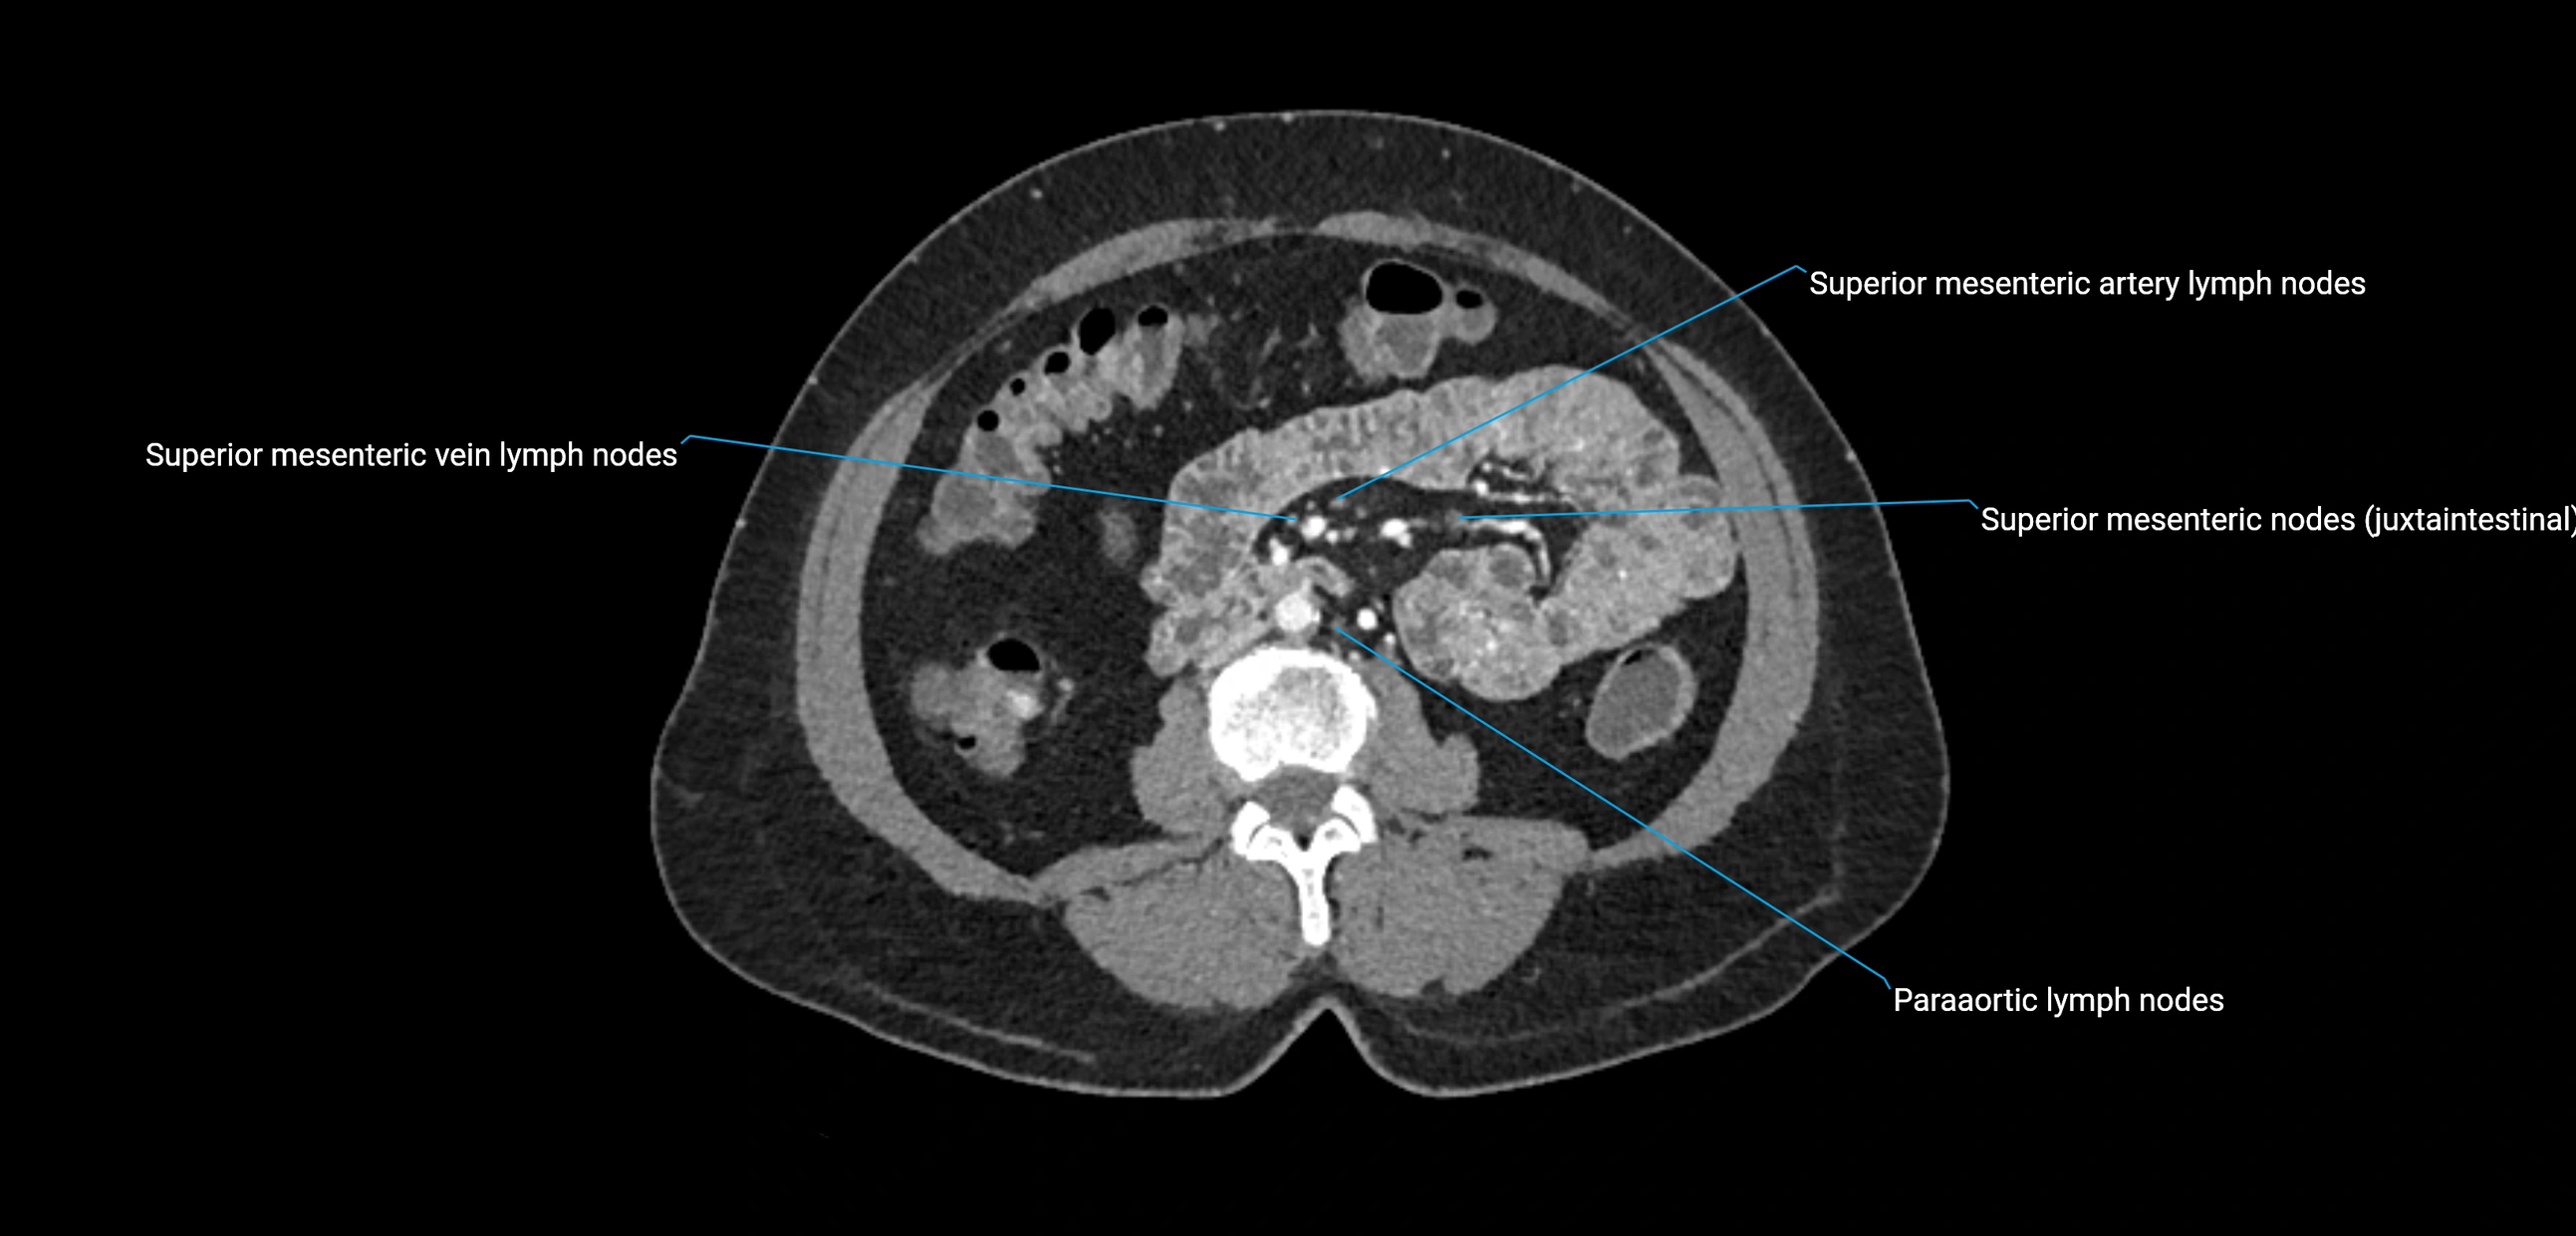

CT Appearance

CT Pre-Contrast:

• Nodes appear as soft-tissue density nodules adjacent to the aorta and IVC

• Calcification may be seen in chronic infections (e.g., tuberculosis)

CT Post-Contrast:

• Normal nodes enhance homogeneously

• Malignant nodes may show heterogeneous enhancement, central necrosis, or conglomerate formation

• Size >1 cm short axis is suspicious, though morphology and distribution are equally important